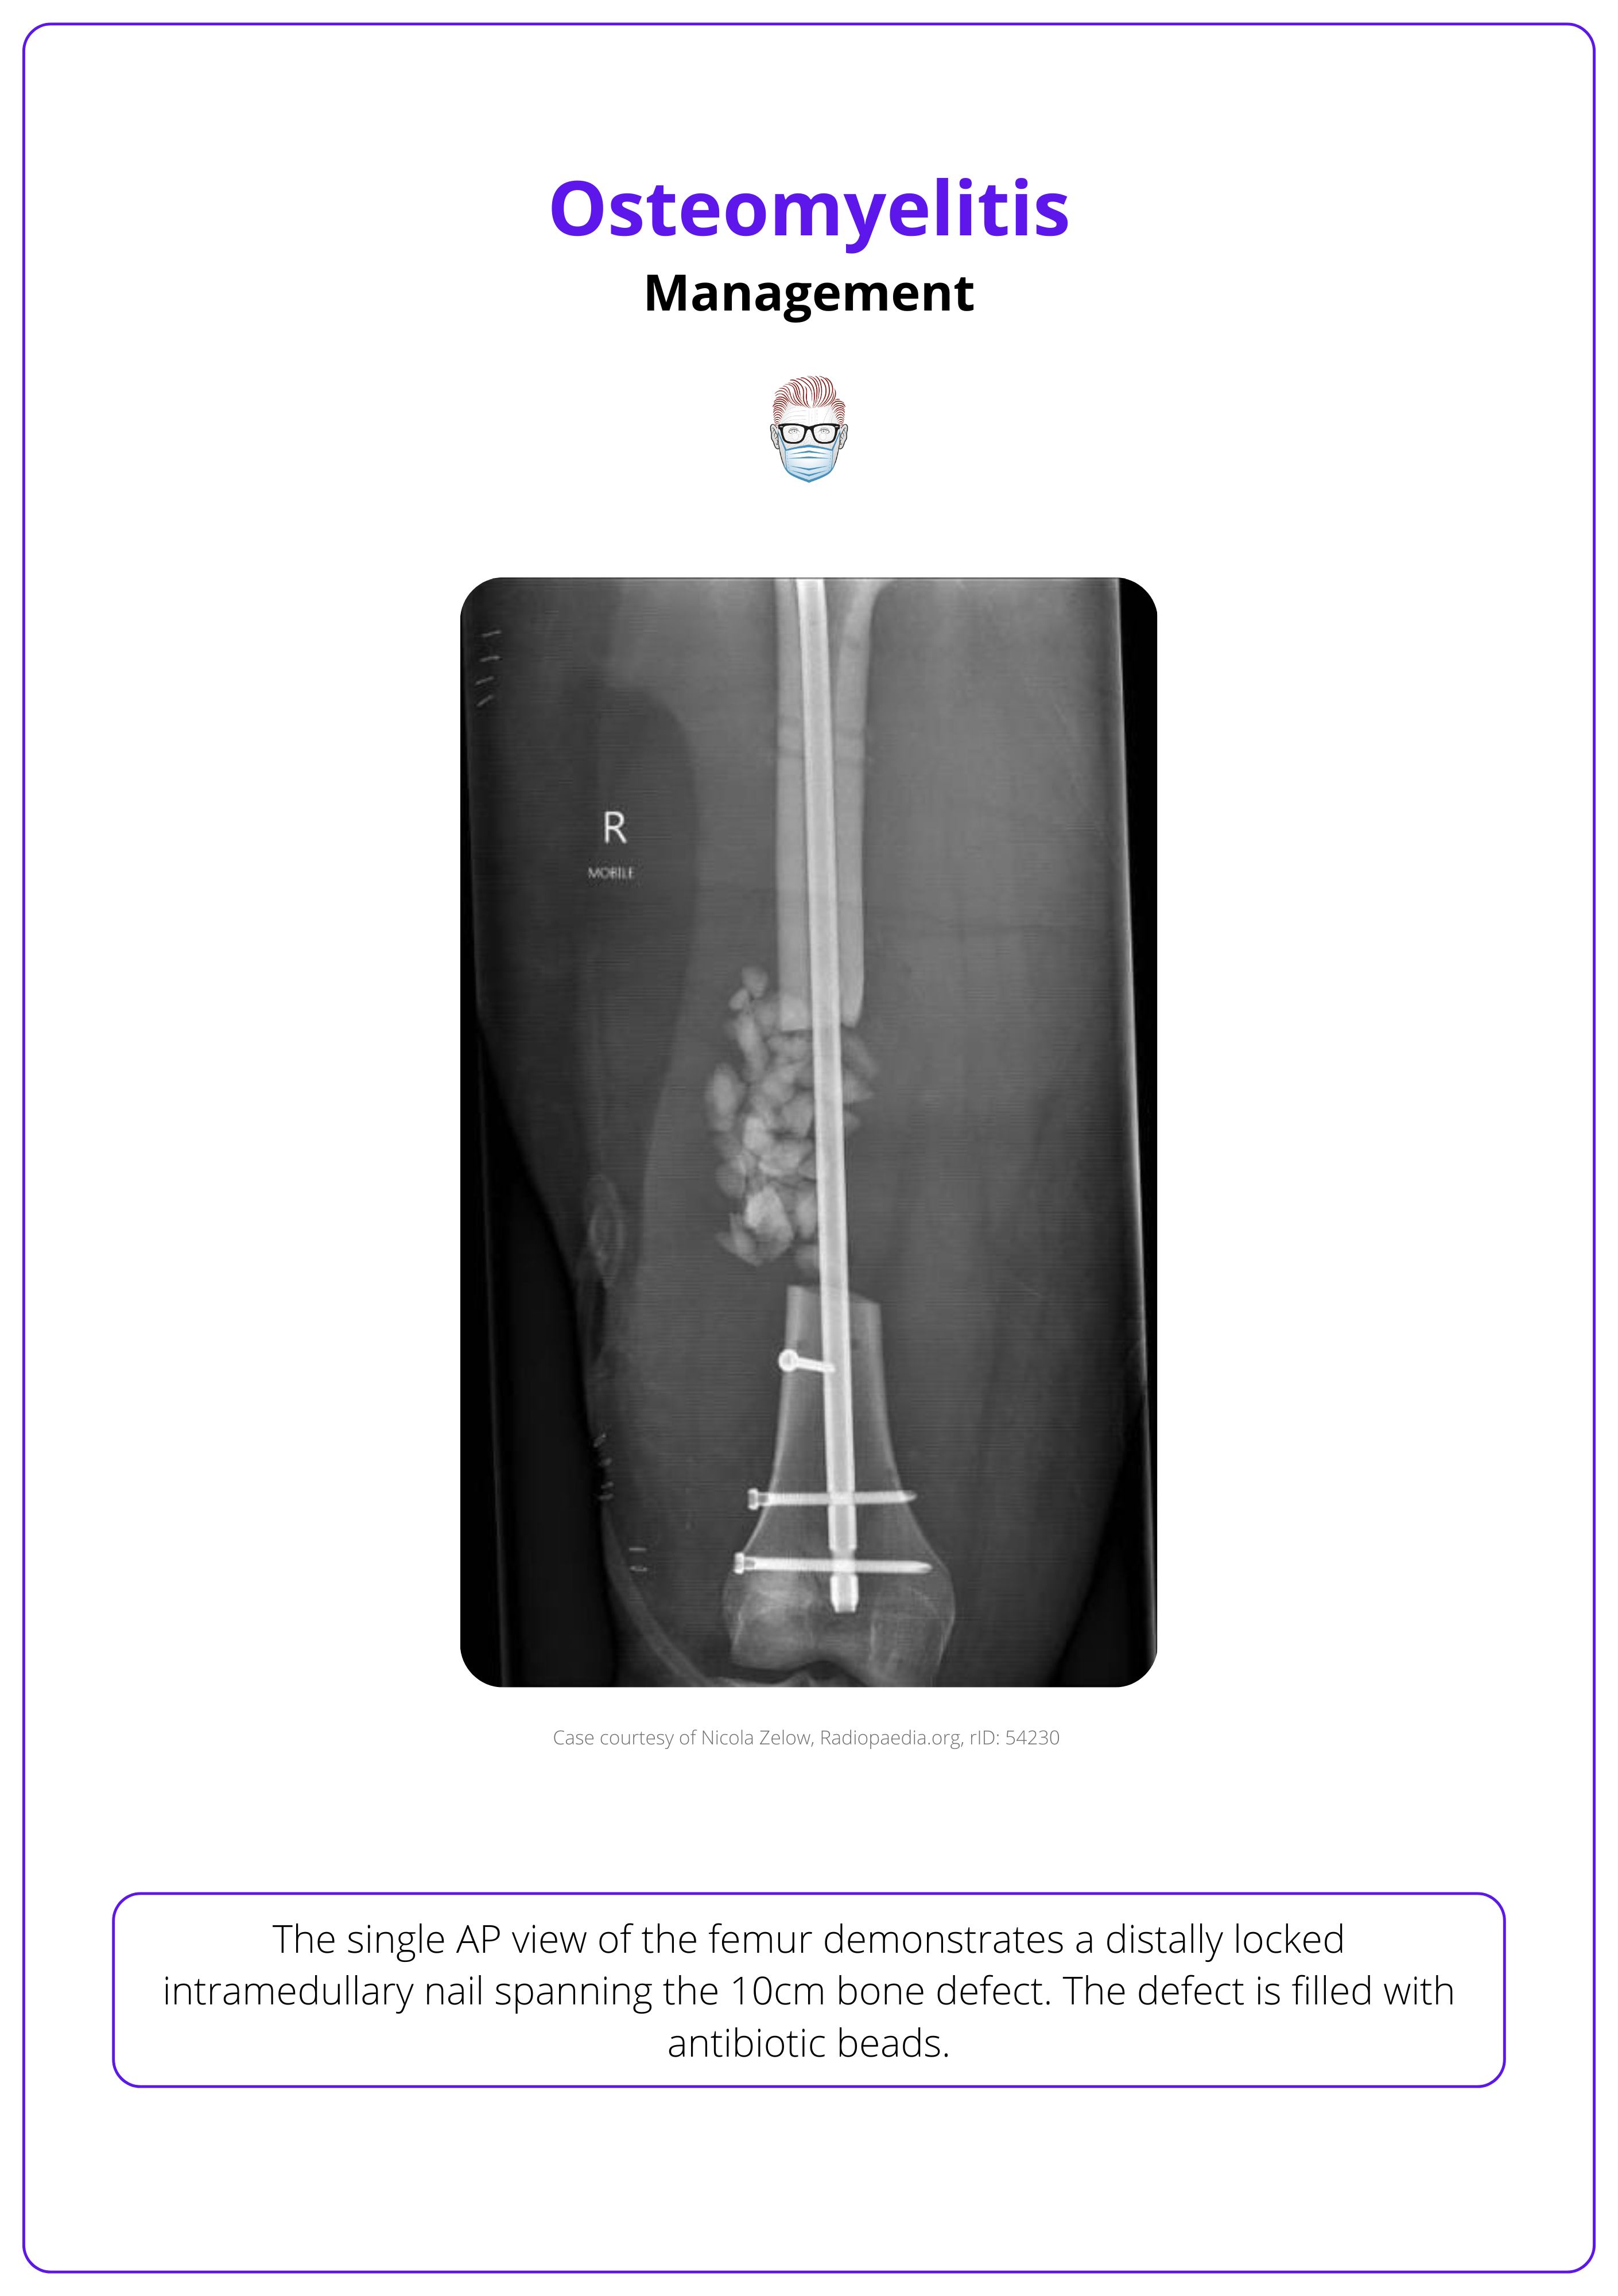

Subacute and Chronic Osteomyelitis

Subacute and chronic osteomyelitis requires a combined approach, addressing both the infection and any associated bone or soft tissue defects.

Surgical Debridement

- Bone Biopsies: Should be taken before starting antibiotics to avoid masking pathogens.

- Pre-operative Imaging: Guides the extent of debridement.

- Debridement Procedure: All infected tissue, abscesses, and necrotic bone must be meticulously removed.

Reconstruction

- Soft Tissue Coverage: Essential to promote healing, prevent recurrence, and enhance antibiotic delivery.

- Tissue Flaps: Local or distant flaps may be used to cover defects, ensuring robust coverage for optimal recovery.

Adjunctive Measures

- Antibiotic-Impregnated Materials: Sutures, spacers, and bone substitutes can assist with localized infection control.